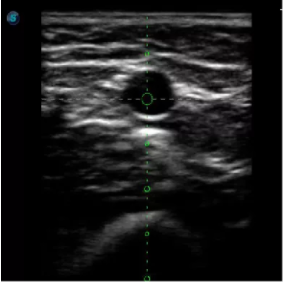

1生殖專用探頭

傳統(tǒng)腔內(nèi)探頭采用直柄設(shè)計(jì),在搭配穿刺架使用時(shí),手術(shù)空間小,不易操作;生殖專用的曲柄探頭,探頭柄采用彎曲成角度設(shè)計(jì),可實(shí)現(xiàn)監(jiān)視、取卵兩不誤,搭載穿刺架時(shí),可以清晰顯示穿刺針的進(jìn)針過(guò)程、深度和位置,實(shí)時(shí)監(jiān)視取卵全過(guò)程,保障取卵操作精準(zhǔn)與安全。

取卵臨床圖